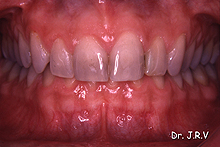

| Fotos

2C, 2D y 2E.- Resolución del caso con la colocación de carillas

de porcelana de premolar a premolar. |

En algunos casos, el uso combinado de técnicas ortodóncicas

con restauraciones indirectas cerámicas resolverá favorablemente

el caso a tratar9.